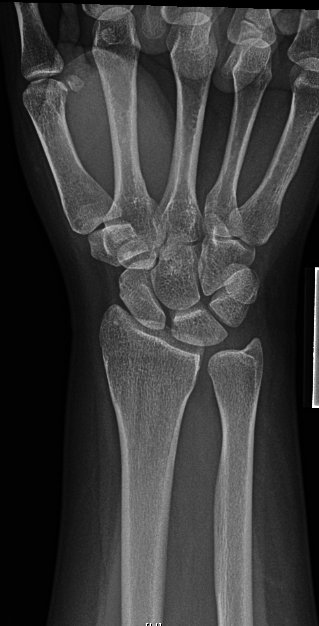

24y/o healthy RHD F who works in an office job fell roller skating.

Nothing surprising on exam

Given frx pattern and risk for concomitant SL injury (and ?SL widening), started scratching the ole’ noggin.

Couldn’t do dynamic (grip) view for injured side so we went for a contralateral comparison. Subtle differences if any…